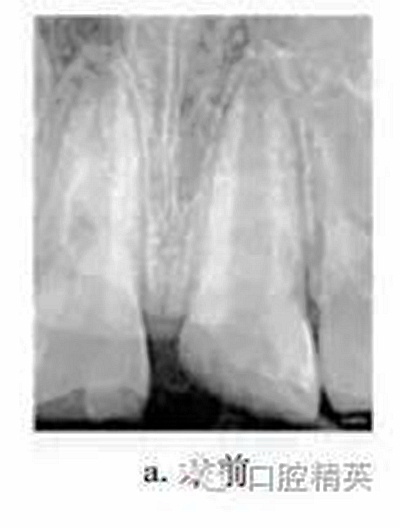

患者男,10歲。2011-06因上頜中切牙外傷就診于我院牙體牙髓病科?;颊咦允?d前患牙外傷,冷熱刺激敏感,但未行治療。檢查:11牙冠近中切角缺失,切緣釉質(zhì)缺損,無松動,探敏感,叩(+),冷熱無明顯不適;21牙冠近中斜折,邊緣銳,髓腔暴露,探診出血,探痛明顯,牙髓電活力測試(-),叩(+),無松動,牙齦未見異常,上唇腫脹。X線片示:21冠部缺損及髓,牙周膜腔增寬,根端管壁呈平行狀,根尖孔未閉合(圖a)。診斷:11釉質(zhì)缺損;21冠折。